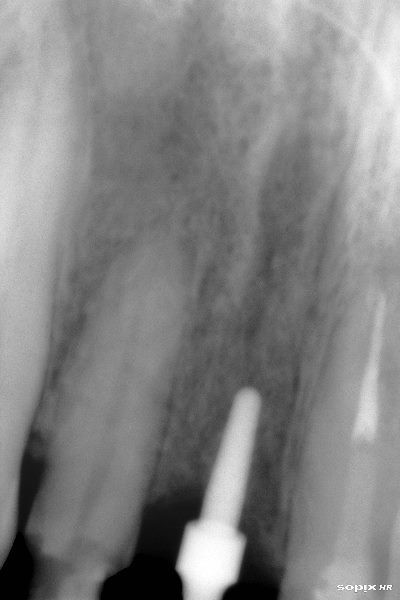

Se coloca poste de impresión

Cuatro meses después se coloca tornillo de cicatrización